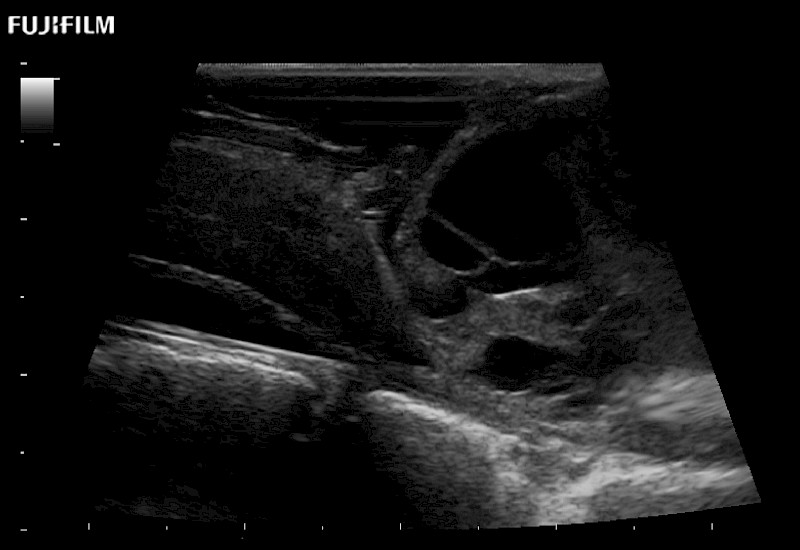

Extraordinary high-resolution digital imaging

Exceptional transducers

for use during: Cranial guidance, Burr-Hole guidance, Spinal Cord guidance, Pituitary guidance, Micro-Surgery guidance